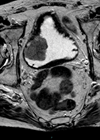

An 80-year-old gentleman, with a smoking history, presented with lower urinary tract symptoms and visible haematuria. An ultrasound scan of renal tract and flexible cystoscopy showed 5cm bladder wall thickening very suspicious for bladder cancer. The patient subsequently underwent transurethral resection of bladder tumour (TURBT) and histology revealed a non-urothelial cell carcinoma pathology. The patient presented a few months later with vertebral metastasis and passed away.

Figure 4.

- Given the presentation the likely diagnosis is small cell carcinoma of bladder. Small cell carcinoma accounts for approximately 1% of primary bladder malignancy in the UK [1]. This is a rare, aggressive, poorly differentiated neuroendocrine tumour. Neuroendocrine tumours are generally classified into carcinoid tumours and neuroendocrine carcinoma, which is subclassified into small cell carcinoma and large cell neuroendocrine carcinoma (rare) [1]. Chromogranin is positive in 50% of cases of small cell carcinoma. Histopathological findings include sheets and nests of small to medium-sized cells with hyperchromatic nuclei, inconspicuous nucleoli, and scant cytoplasm with extensive areas of coagulative necrosis. Genuine small cell carcinoma of the bladder is rare and is usually mixed with another histologic subtype (most commonly urothelial carcinoma) [6]. Small cell carcinoma of the bladder has a more aggressive behaviour and carries a worse prognosis as patients present at a later stage [6].

- The presenting symptoms are those of visible haematuria and dysuria (second most common symptom). Other non-specific symptoms include urinary tract obstruction, abdominal pain, recurrent UTIs and weight loss. Paraneoplastic symptoms have been reported rarely such as hypercalcemia and ectopic ACTH secretion. Immunohistochemistry plays a major role in the diagnosis using neuroendocrine markers.

- Due to its aggressive behaviour, a multimodal treatment strategy is recommended which may include radical or partial cystectomy, radiation therapy, and neoadjuvant / adjuvant chemotherapy as well as chemotherapy alone.